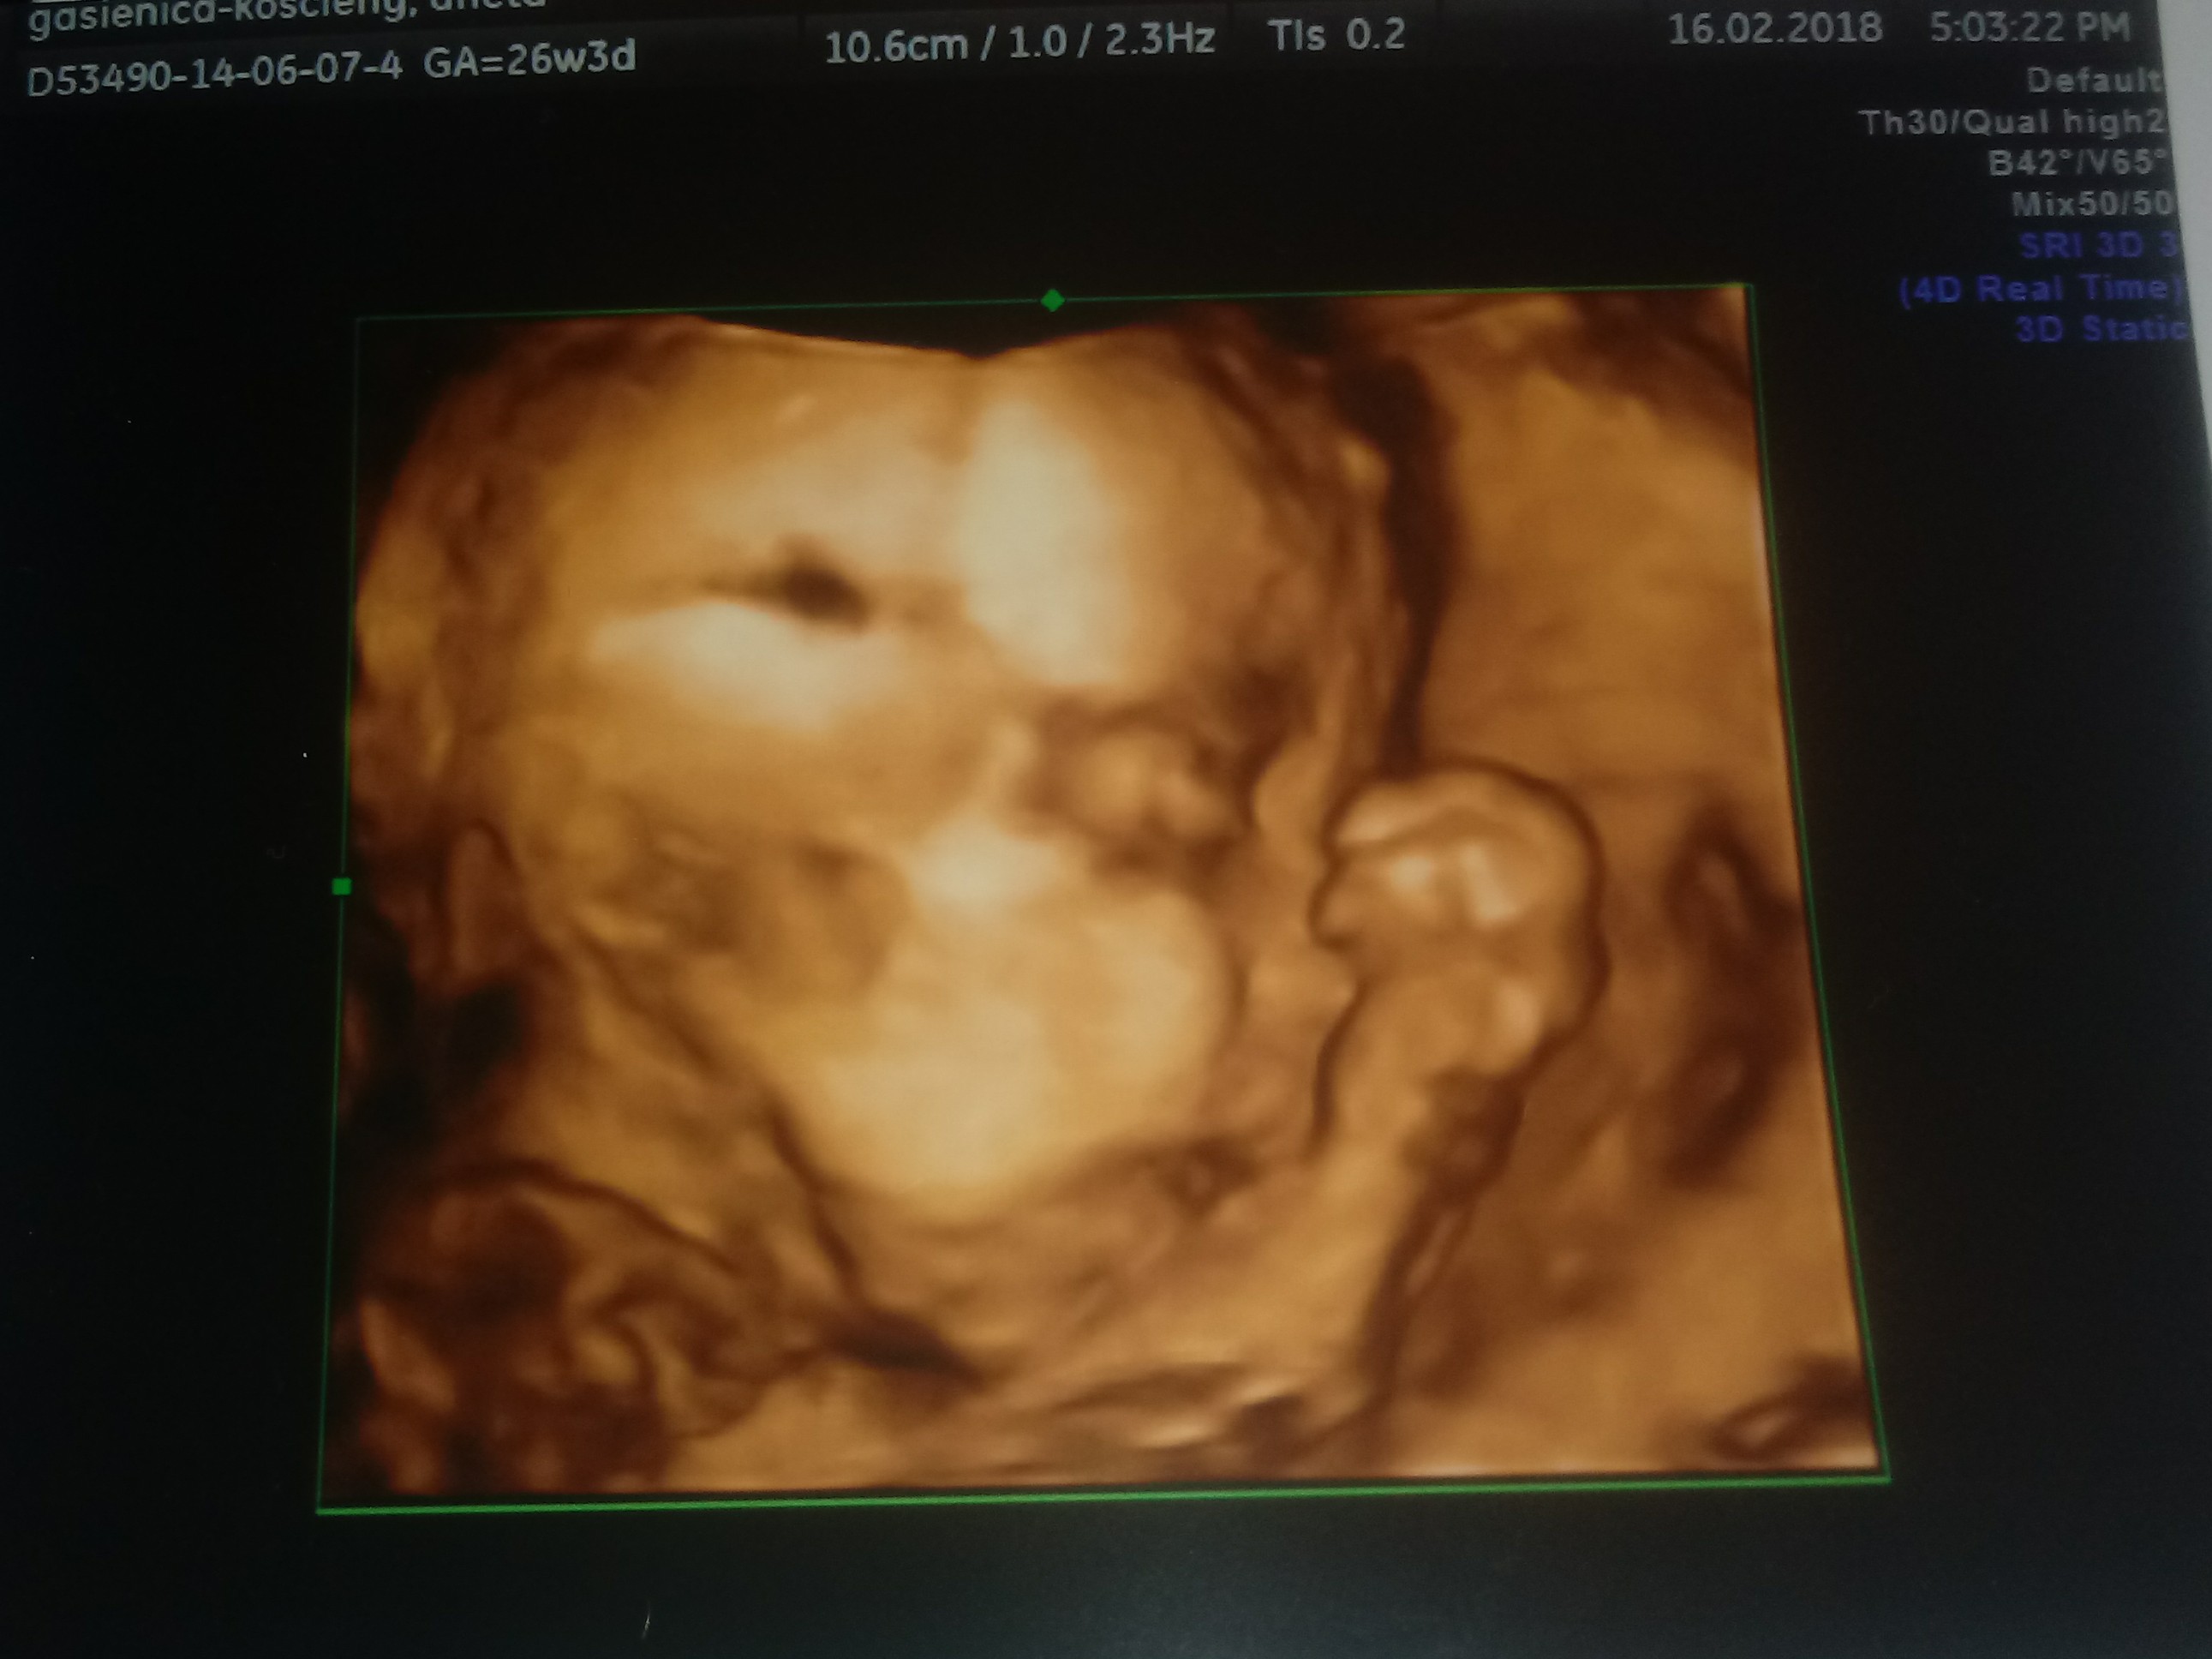

tysia123 to jak bys mogla to daj jutro znac, co bylo mniejsze :\ troszke mnie uspokoilas bo ten gin nawet nie powiedzial ze moze byc tak ze dzidzia siusiu zrobila... Wrr.. Za 2 tyg mam wizyte u swojego i zobaczymy... Mam nadzieje ze wszystko ok bo zamiast sie cieszyć to jesteśmy zdenerwowani..i mala jeszcze obrócila sie ..

Brzuszkowa właśnie to usg4d bylo prywatnie... A tak to chodze na NFZ i moj gin na NFZ jest naprawde dobrym gin w Zakopanem

i moze tak powiedział ten gin zeby przyjść znowu prywatnie .. Bo nic nie wytłumaczyl nam czym moze byc to spowodowane ani nic.. Tylko ze brzuszwk jest maly.. Juz wiecej Wy mi podpowiedzialyscie